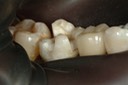

Alan Chinn #2 - 5 finish